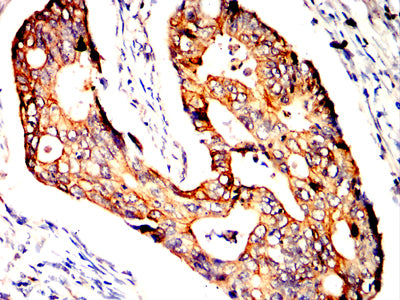

Immunohistochemical analysis of paraffin-embedded human colon cancer tissues using POU5F1 mouse mAb with DAB staining.

Immunohistochemical analysis of paraffin-embedded human rectum cancer tissues using POU5F1 mouse mAb with DAB staining.